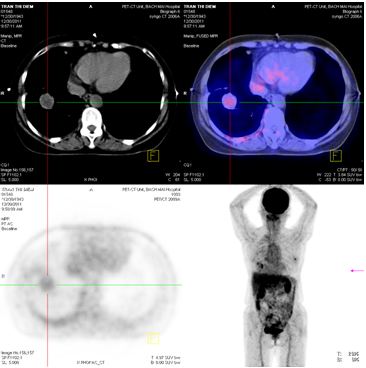

Chụp PET/CT:

Hình 4: Hình ảnh PET/CT có khối u thùy dưới phổi phải 2,6 × 2,8 cm, Max SUV= 5,32

Hình 5: Hình ảnh PET/CT có tổn thương cung sau xương sườn số 5 bên trái, và khối u não vùng đỉnh trái

Chụp PET/CT toàn thân sau 6 tháng điều trị:

Trước điều trị : Khối u thùy dưới phổi phải 2,6 × 2,8 cm, Max SUV = 5,32

Sau điều trị 6 tháng: U tan gần hoàn toàn

Hình 7: Hình ảnh PET/CT toàn thân sau 6 tháng điều trị: Khối u phổi tan hoàn toàn

Trước điều trị: tổn thương thùy đỉnh trái 2 cm

Sau điều trị 6 tháng: tổn thương tan hoàn toàn

Hình 8: Hình ảnh PET/CT toàn thân sau 6 tháng điều trị: Khối u não vùng đỉnh trái tan hoàn toàn.

Trước điều trị: Tổn thương cung sau xương sườn số 5 bên trái